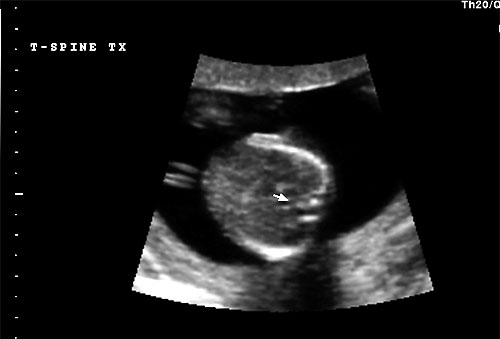

Normal 16 week transverse view of thoracic spine |